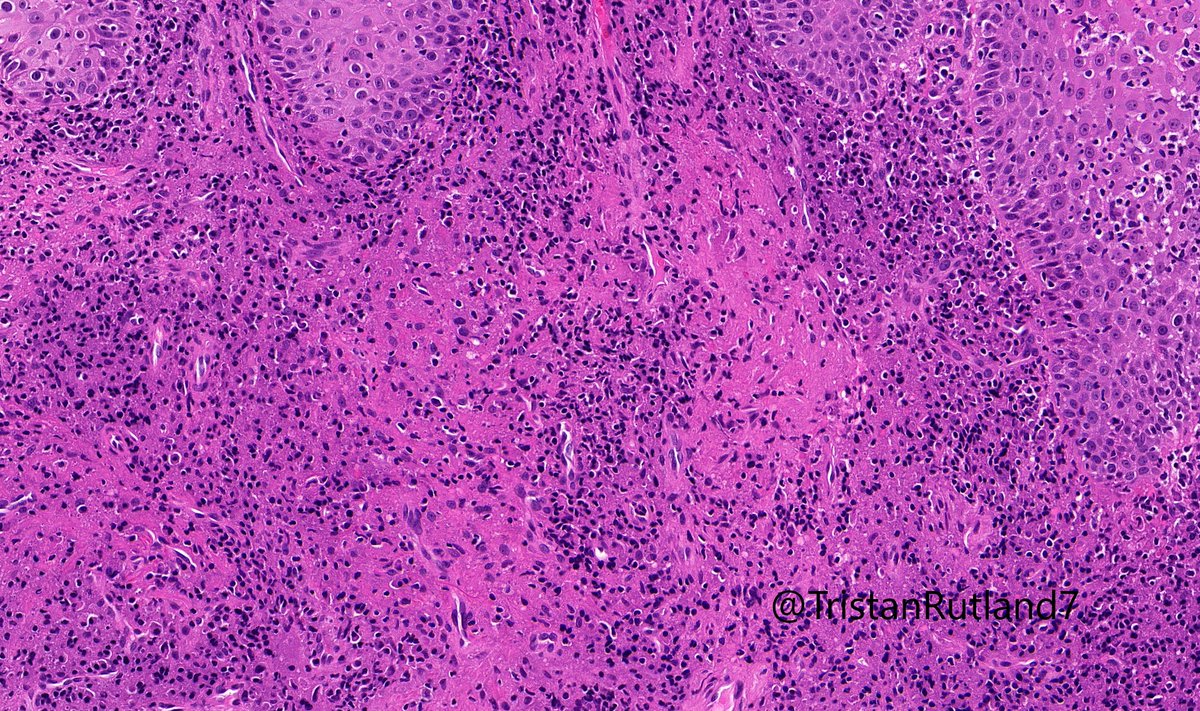

Young adult with lip lesion. Special stains negative. Diagnosis? Answer & More info: kikoxp.com/posts/9905 More posts from Dr. Rutland @TristanRutland7 kikoxp.com/tristan_rutlan… #pathology #pathTwitter #medTwitter #oralpath #ENTpath

kiko4docs's tweet image. Young adult with lip lesion. Special stains negative. Diagnosis?

Answer & More info: kikoxp.com/posts/9905

More posts from Dr. Rutland @TristanRutland7 kikoxp.com/tristan_rutlan…

#pathology #pathTwitter #medTwitter #oralpath #ENTpath